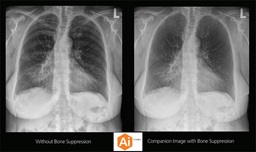

CARESTREAM Image Suite V4 MR11 has set a new standard for workflow efficiency, offering a robust set of features and functionalities to enhance clinical confidence in healthcare professionals. Using an auto-generated companion image from a single exposure, leverage a range of image processing options to increase diagnostic accuracy and enhance patient care.